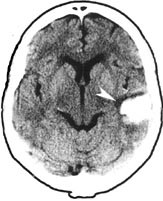

3.6. 1998 fikk han akutt motorisk og sensorisk afasi. Cerebral computertomografi viste hematom temporalt på venstre side (fig 1). Hjerneblødningen ble vurdert å være hypertensivt betinget, og det ble startet med antihypertensiv behandling. 22.8. 1998 fikk han akutt vertigo, kvalme og lett høyresidig ekstremitetsataksi. Over cor hørtes en svak systolisk bilyd. Cerebral magnettomografi viste bilaterale infarkter supra- og infratentorielt, mest uttalt i høyre cerebellum (fig 2), samt rest etter tidligere hematom temporalt på venstre side. EKG viste sinusrytme med venstre ventrikkel-hypertrofi. Pasienten fikk feber og forhøyede infeksjonsparametere (CRP = 170 mg/ml, SR = 70 mm/t og LPK = 21 × 10⁹/l). Antibiotikabehandling ble startet på mistanke om endokarditt. Det var imidlertid ingen oppvekst i flere blodkulturer. Transtorakal og transøsofageal ekkokardiografi viste et stilket myksom utgående fra venstre atrium. Myksomet ble ekstirpert. Mikroskopisk undersøkelse viste myksoid vev, uten tegn til malignitet. Ved senere kontroller ble det ikke påvist residiv av myksom eller flere cerebrale embolier. Pasienten ble 3.2. 1999 innlagt igjen pga. et epileptisk anfall. EEG viste klare cerebrale funksjonsforstyrrelser lokalisert frontotemporalt på venstre side. Han fikk behandling med karbamazepin og har siden vært anfallsfri.

I en studie av 12 pasienter med myksom var hemiparese, afasi, synsforstyrrelse, demens og vertigo første manifestasjon hos fire (8). Vår pasient fikk først afasi, og det ble påvist hematom temporalt på venstre side. Dette har sannsynligvis vært hypertensivt betinget, siden hematomet var manifest i akuttfasen. Det er mindre sannsynlig at det har vært en hemoragisk transformasjon av et iskemisk infarkt betinget i emboli fra myksom i venstre atrium. Senere fikk pasienten vertigo og ataksi, og det ble påvist multiple infarkter av ny og eldre dato.